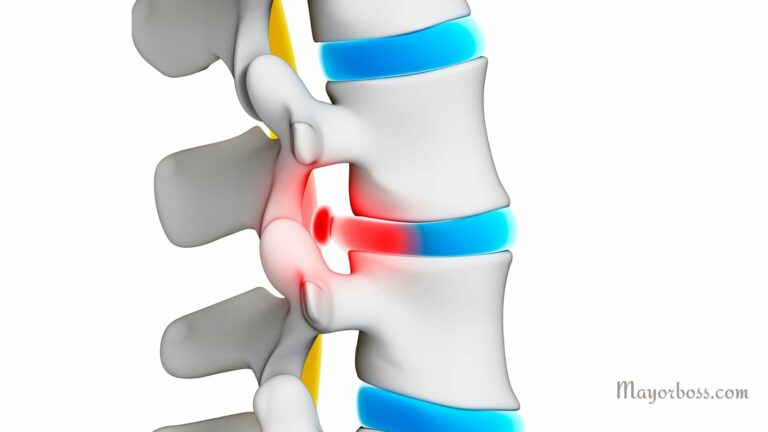

What Is A Bulging Disc?

What Is a bulging disc? A bulging disc…